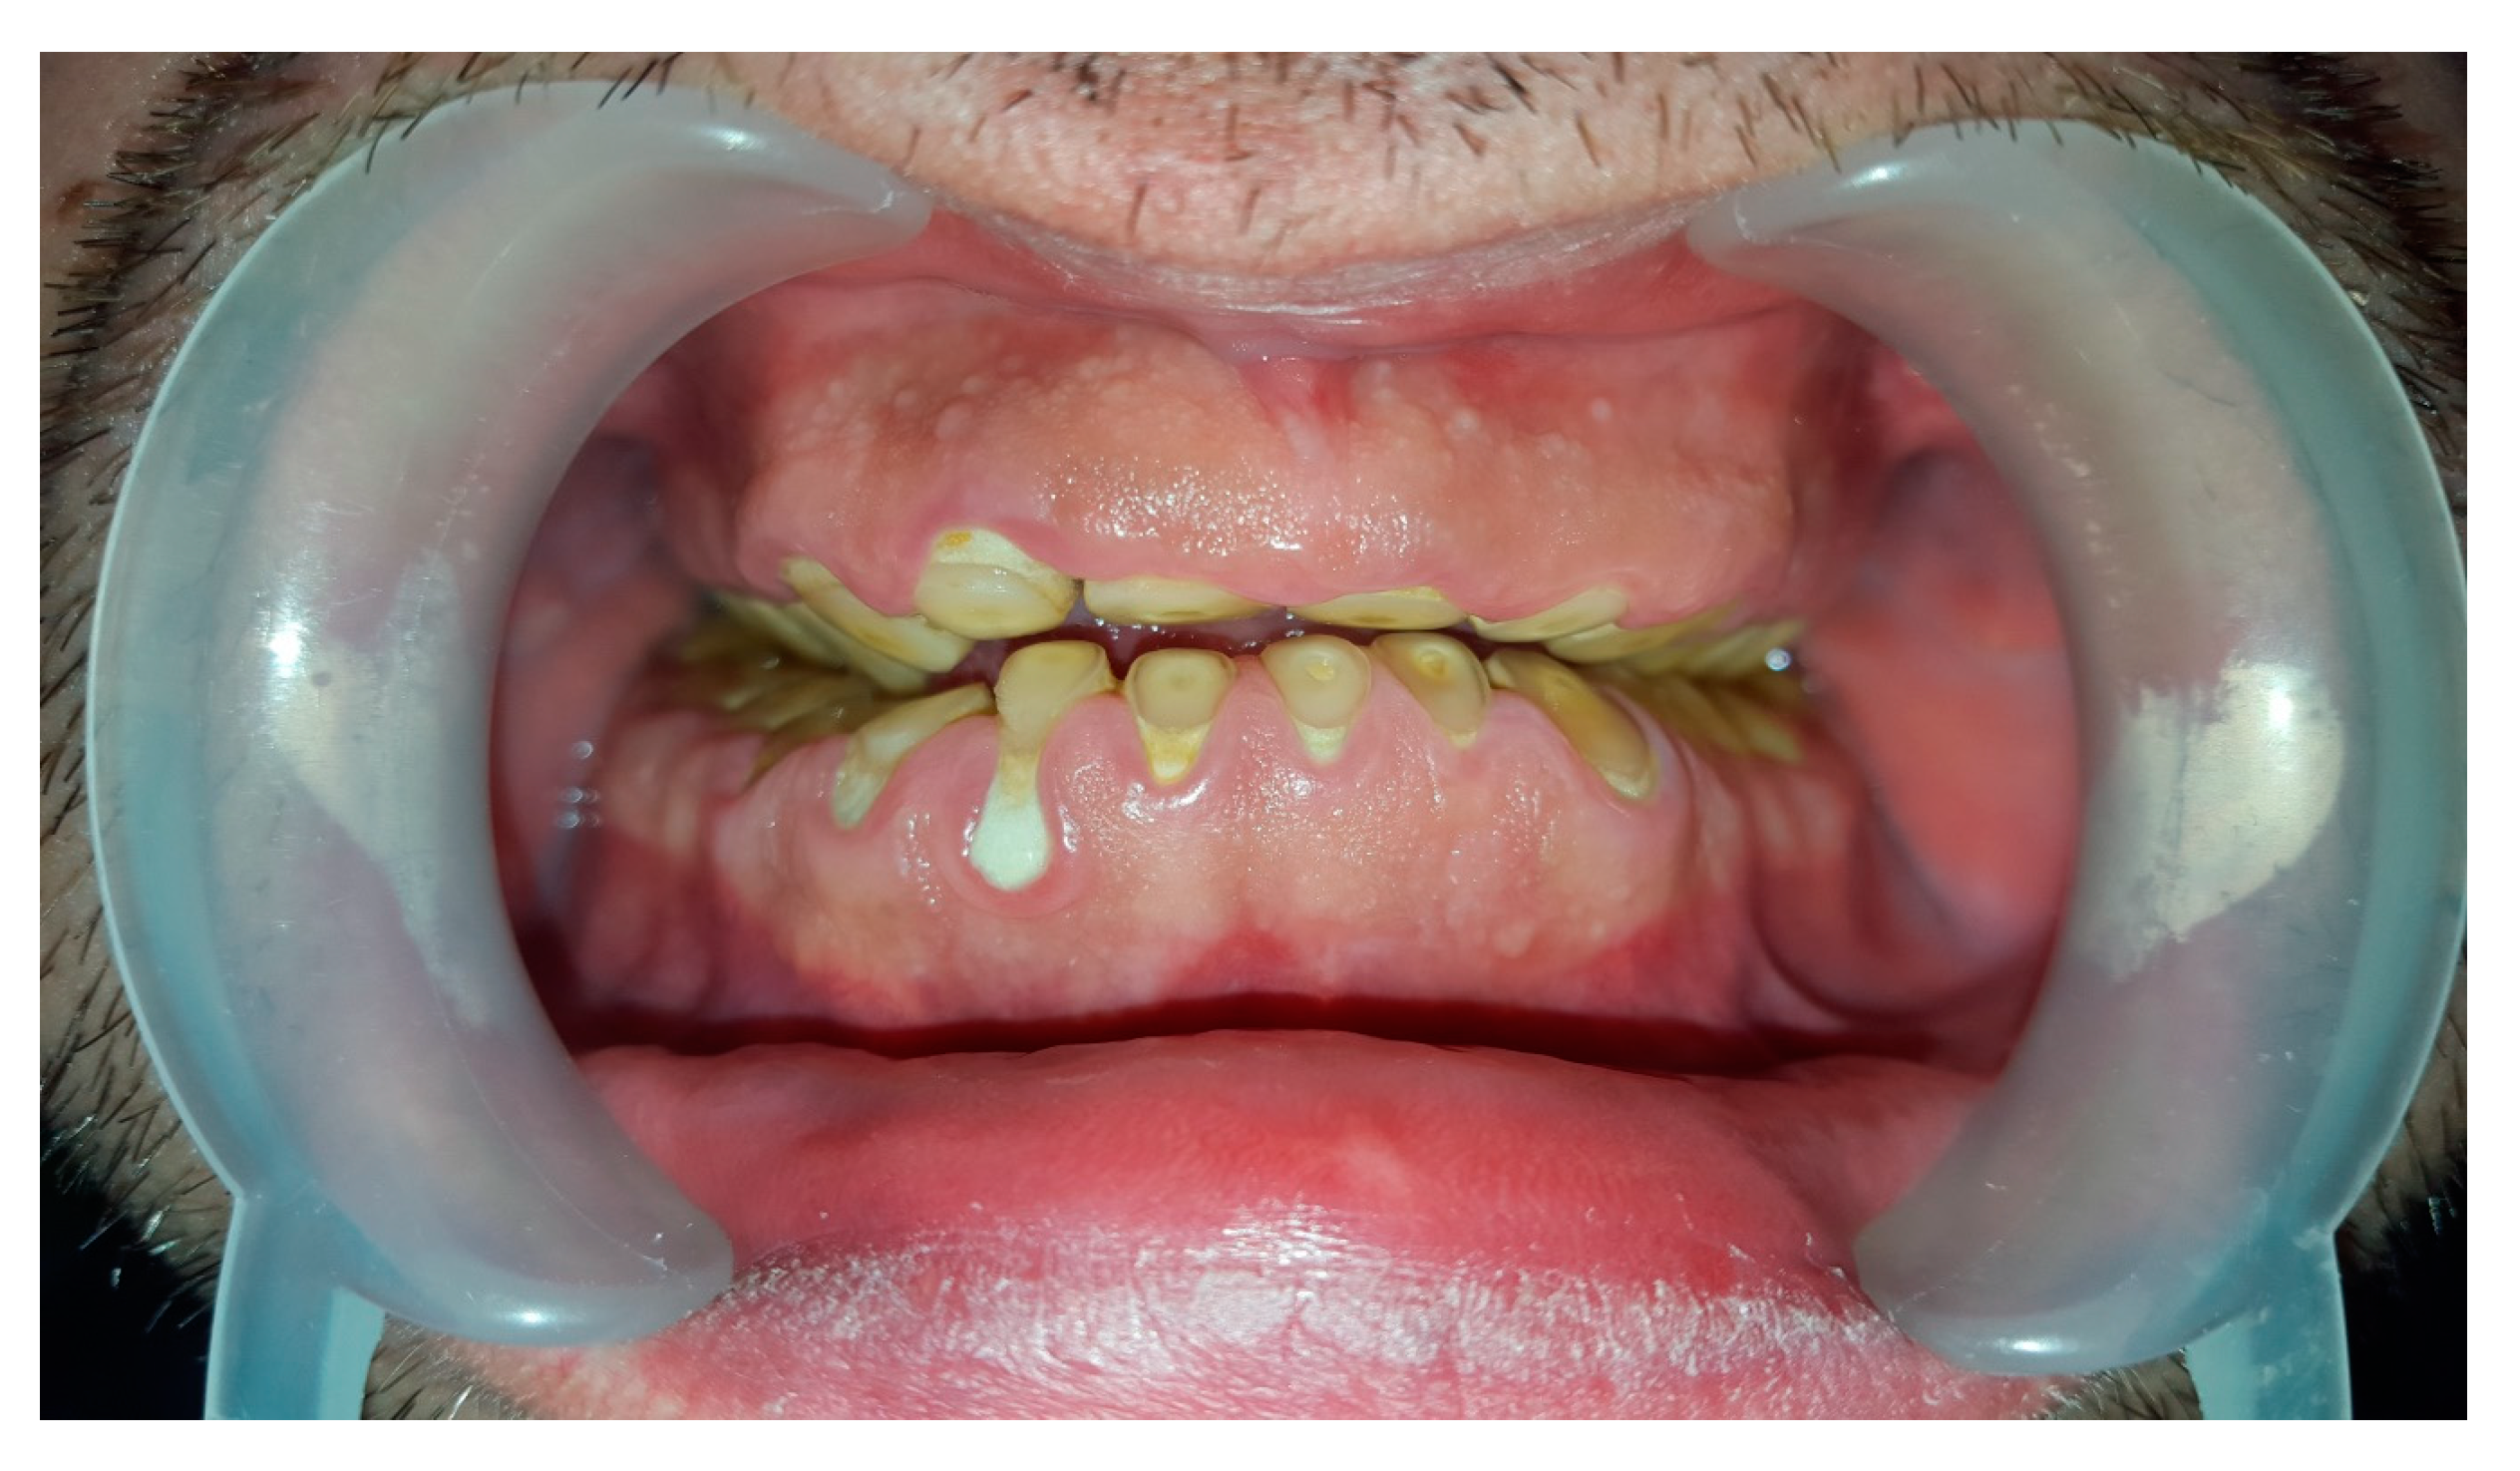

Dental examination confirmed bilateral hypertrophy of masseter muscles and teeth wear of 4th stage in Tooth Wear Index (Figure 2).

Figure 2. Tooth wear in presented bruxist patient.